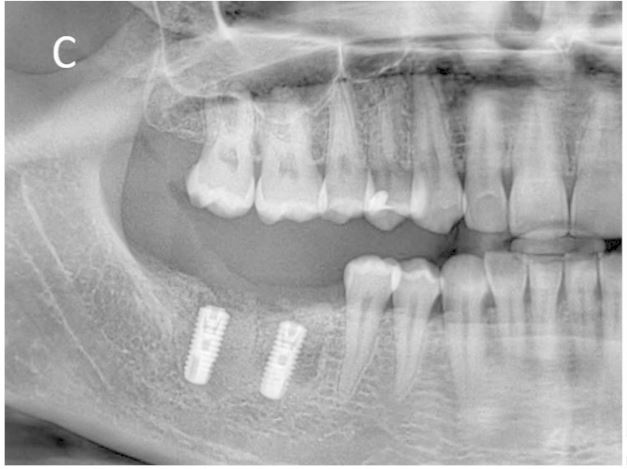

(A ) Right mandibular first and second molars with chronic periapical pathology due to unsuccessful endodontic treatments. (B ) Extraction of teeth, placement of immediate implants and filling of socket cavities with guided bone regeneration (1st postoperative week). (C ) Postoperative 5th month panoramic radiograph image. (D ) Follow-up radiograph at 12 months after completion of prosthetic restorations